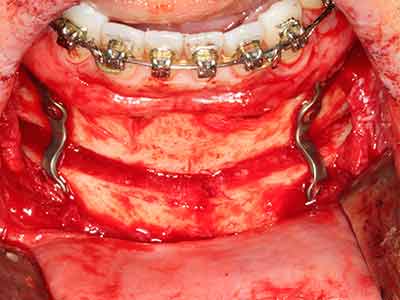

Il tessuto osseo non è semplicemente una struttura minerale, ma contiene anche una percentuale significativa di fibre di collagene. Ciò significa che non possiede solo una buona forza di compressione, ma anche un certo livello di flessibilità che è possibile sfruttare durante l'esecuzione degli accrescimenti di osso. Nella procedura di espansione classica con incisione ossea, la cresta alveolare atrofizzata viene incisa longitudinalmente ed espansa con cautela dopo aver raggiunto una profondità di osteotomia adeguata (figg. 13-16), idealmente senza una sostanziale rimozione del periostio (Brugnami, Caiazzo et al. 2014, Stricker, Fleiner et al. 2014). I sistemi a piastra e vite con distanza di espansione incrementale si sono dimostrati efficaci nella separazione delle due lamelle ossee restando al di sotto della soglia di frattura. In generale, sono richieste larghezze dell'osso residuo di almeno 3-4 mm (Chiapasco, Zaniboni et al. 2006) per garantire un'adeguata flessibilità e una copertura sufficiente dell'osso per gli impianti futuri. Se necessario, un'osteotomia di rilascio verticale su uno o più lati può migliorare la flessibilità. Una combinazione con ulteriori tecniche di accrescimento, in particolare dal lato buccale, è stata descritta come un'alternativa alla tecnica classica.

La procedura di incisione è particolarmente atraumatica e non comporta una perdita significativa di dimensione durante l'utilizzo delle seghe piezoelettriche, così come non si notano differenze rilevanti tra impianti in mandibole incise e impianti in una cresta alveolare senza deficit osseo (Chiapasco, Zaniboni et al. 2006, Danza, Guidi et al. 2009). Una sufficiente irrigazione continua è essenziale, tuttavia, in particolare con incisione profonda e localmente ristretta, per prevenire la sollecitazione termica nelle regioni apicali dell'osteotomia.